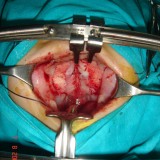

Acute Scrotum (Right scrotal Abscess)

Torsion of Left Undescended Testis (Pre operative and Operative Photo)

Acute Scrotum

Torsion Testis (Pre and Per operative photo)